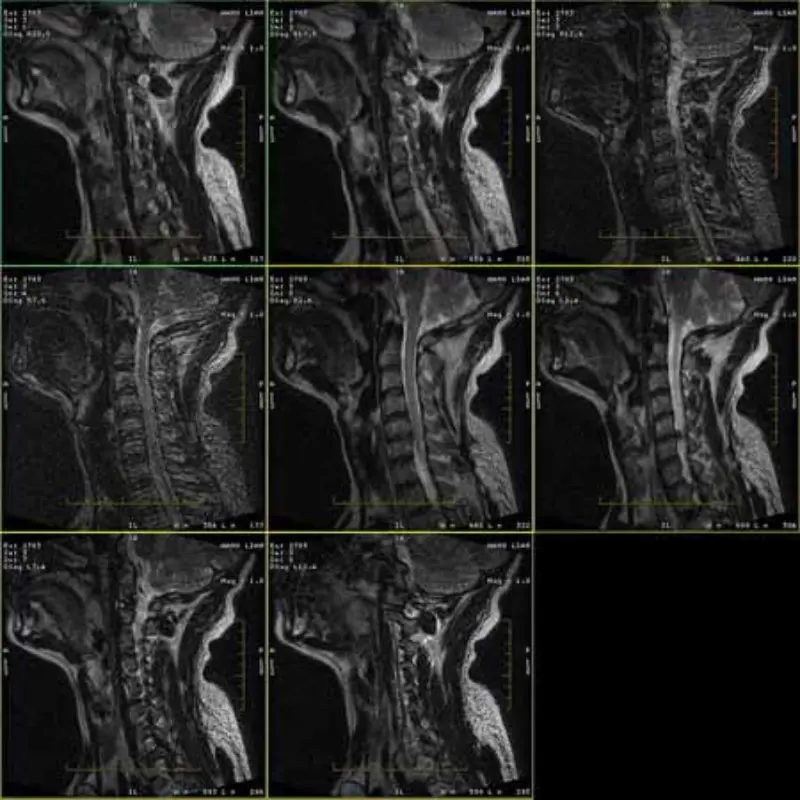

FRFSE اور GRE پروٹوکول کی تصاویر میں بھوت ہے اور بعض اوقات کم SNR تصاویر ایک سیریز میں ظاہر ہوتی ہیں۔ لیکن SE پروٹوکول امیجز نارمل ہیں۔

براہ کرم منسلک تصاویر دیکھیں۔